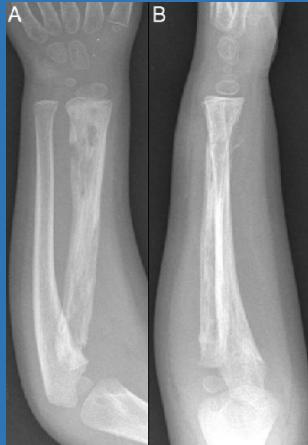

| Compartment Syndrome | Increased pressure within a closed fascial compartment, leading to reduced tissue perfusion, hypoxia, and irreversible muscle and nerve damage. Causes: Fractures (especially tibia/forearm), severe soft tissue trauma, arterial injury, burns, tight casts/dressings, post-ischemic reperfusion swelling, IV fluid extravasation, and bleeding disorders (e.g., hemophilia). High-Risk Notes: Pain may be absent in altered consciousness, children (monitor analgesia response), polytrauma, sedated/epidural cases, or concomitant nerve damage. Open fractures do not always decompress pressure. Gross/Clinical: -tense, shiny leg swelling with blisters in compartment syndrome.Imaging: - Intraoperative fasciotomy | History/Symptoms: Pain out of proportion to the injury (e.g., a “bursting” sensation), which is not relieved by analgesia. Clinical Features (The 5 P’s): - Pain with passive stretch (early, key sign; e.g., ankle dorsiflexion for leg, wrist for forearm). - Paresthesia (early). - Palpable tense swelling (shiny skin, blisters: clear=mild, serosanguinous=severe, bloody=worst; dusky/pallor skin). - Pallor, Paralysis, Pulselessness (late, ominous signs; pulses often palpable until late). Investigations: Primarily a clinical diagnosis (high suspicion key). Compartment pressure measurement can confirm: absolute pressure >30 mmHg or Delta Pressure (Diastolic BP - Compartment P) ≤ 25 mmHg. | Initial: ABCs, supplemental oxygen. Remove all circumferential dressings, casts (bivalve to skin), and splints. Elevate the limb to heart level (not above; higher reduces inflow). Correct any hypotension. Surgical: Urgent Fasciotomy if no response within 1h or confirmed pressure (prophylactic in high-risk like major osteotomy). Release all compartments/skin with long incisions; debride necrotic muscle via 4C’s (early: pink/red, soft, contracts/bleeds on pinch; late: dark, firm, no response); preserve neurovascular. Wound open (bulky dressing/splint, VAC, or boot-lace gradual closure); repeated inspections x48h; coverage in 3-5 days (skin graft usual; flap if nerves/vessels/bone exposed). | Cellulitis, Deep Vein Thrombosis (DVT), Arterial occlusion, Severe soft tissue injury without compartment syndrome; equivocal cases in polytrauma. | Complications: Volkmann’s ischemic contracture (permanent deformity, weakness, sensory loss, chronic pain). Contraindications (Fasciotomy): Confirmed >48h (irreversible damage, high infection risk from dead tissue); crush injuries with already necrotic muscle. |

| Open Fracture | A fracture with a breach in the overlying skin and soft tissues, creating communication with the external environment. All open fractures are considered contaminated (even small punctures; aka compound fracture). Causes: Can result from high-energy trauma (RTAs, falls, firearms; signs: degloving, crush syndrome, bone loss, segmental) or low-energy trauma. Contamination risk higher with farm/soil injuries, bites, delayed presentation (>12h), fecal/oral/soil/water exposure. Mechanism: Low/high velocity missiles (cavitation >300 m/s); in-out (cleaner) vs. out-in (dirtier). Gross/Clinical: ![]() | History: Mechanism of injury (energy, time, place, type/impact method), consciousness, wound size/bleeding amount, other injuries (often missed), tetanus status. Assessment: ATLS protocol (ABCDE) first (treat patient, not fracture; exclude shock/brain injury, monitor vitals; viscera exam: ribs=lungs/liver/spleen, pelvis=bladder/urethra). Examine wound (look/feel/move carefully post-splint), check distal neurovascular status, compartment syndrome. Photograph/remove gross contamination; cover with saline dressing. Classification (Gustilo-Anderson): - Type I: <1 cm wound, clean, minimal soft tissue. - Type II: >1 cm wound, moderate soft tissue (no stripping). - Type IIIA: Extensive soft tissue damage, but adequate bone coverage. - Type IIIB: Extensive soft tissue loss with periosteal stripping; bone exposed, requires flap coverage. - Type IIIC: Any open fracture with an arterial injury requiring repair. | Initial (ER): ATLS first. Cover wound with sterile saline-soaked dressing, splint limb, IV fluids (request blood if needed); traction if no distal pulse/deformity. Prophylaxis: Tetanus prophylaxis/serum and broad-spectrum IV antibiotics immediately (culture tissue/blood); clean major contamination. Surgical: Urgent debridement/irrigation within 6-12h (“Dilution is the solution to pollution”; pulse-irrigate 3-6-9L saline; excise non-viable tissue/foreign material, trim skin edges, remove dead muscle/detached bone, preserve N/V). Stabilization: external fixator (preferred severe; replace with cast post-infection); internal if clean/minimal. Wound closure delayed (primary if small/clean; secondary if contaminated/large). Early soft tissue cover. | The diagnosis is typically obvious. Key: Classify severity; identify associated injuries like compartment syndrome, vascular damage, or high-energy signs (e.g., crush). Differentials for contamination: Primary (field debris) vs. secondary (post-fixation if poor debridement). | Complications: Infection (cellulitis, osteomyelitis, chronic with sequestra/drainage, gas gangrene), tetanus; higher with delay/exposure/bites. - embolisms fat, thrombi others.. Case Insight: Unconscious patient (e.g., open tibia post-RTA): ABCDE/cervical collar, distal pulses/traction, admit for debridement; ankle fall: Splint post-ABC, assess neurovascular. |